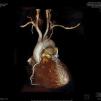

A 59-year-old woman with type 2 diabetes and two-vessel disease had undergone double coronary bypass grafting (CABG) five years previously, with left internal mammary artery (LIMA) to left anterior descending (LAD) artery and free radial graft (Y type), from LIMA to obtuse marginal (OM). Three months ago, the patient began to suffer angina and episodes of dizziness after upper limb exercise, followed by a lateral wall myocardial infarction one month ago. Urgent femoral catheterization revealed thrombotic occlusion of the circumflex (Cx) artery; the LAD had an old occlusion and the LIMA could not be catheterized. The right coronary artery (RCA) was normal. Primary angioplasty of the culprit Cx was performed and two bare-metal stents were deployed. The acute chest pain resolved, but angina and dyspnea recurred one week later. Physical examination revealed absent pulses in the left arm. Cardiac CT angiography revealed abrupt occlusion of the left subclavian artery 1.8cm after its origin, proximal to the LIMA and the ipsilateral vertebral artery. Both these arteries supplied a scant flow to the axillary artery (Figures 1 and 2), but the LIMA was well contrasted, with a good anastomosis to the mid LAD (Figures 1, 2 and 3a). The radial (LIMA to OM) anastomosis was totally occluded, only the path of the metal clips being visible (Figure 2). The Cx stent was patent with no signs of restenosis, and the RCA was normal (Figure 3b and c). The right brachiocephalic and left carotid arteries were normal (Figures 1 and 2). A triplex Doppler scan revealed reversal of left vertebral artery flow (Figure 4). A diagnosis of coronary-vertebral subclavian steal syndrome was made.

In this case, a large CT acquisition window was used, ranging from the middle neck region to the diaphragm, to ensure good anatomical coverage, particularly of the proximal supra-aortic vessels, in preparation for possible future surgery. Since the left carotid artery was disease-free, a carotid-left axillary shunt was proposed, without further invasive investigations.